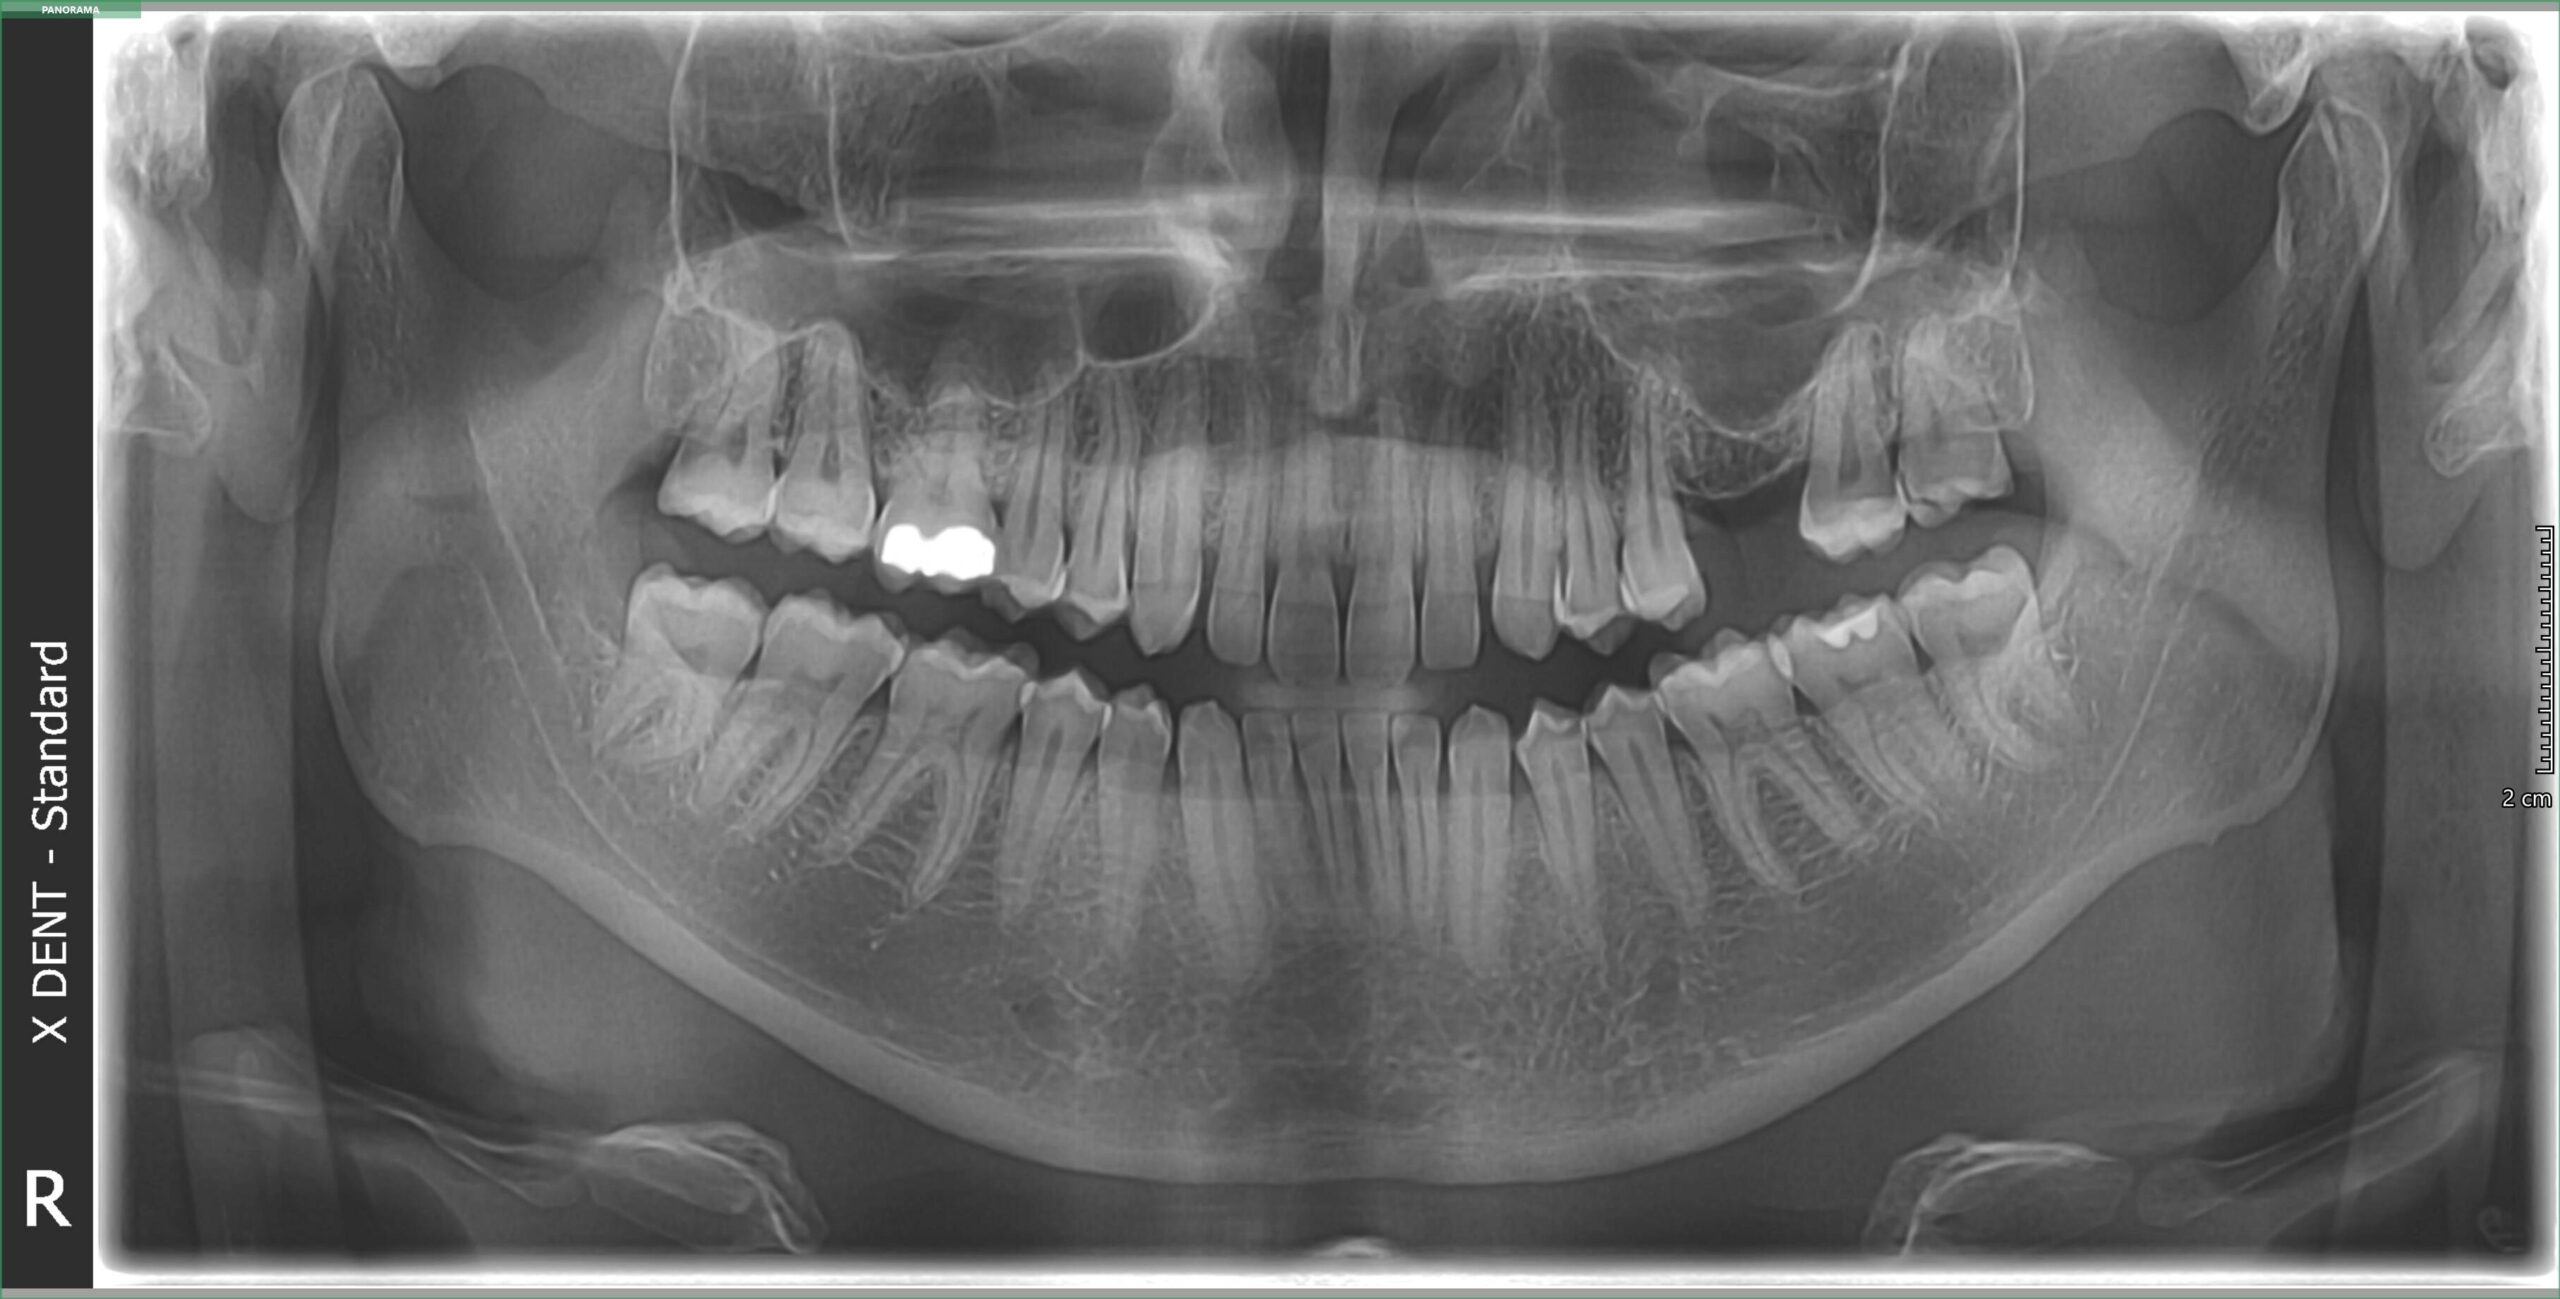

Ortopan snimak, poznat i kao panoramski rendgen zuba (OPG), predstavlja naprednu dijagnostičku metodu koja omogućava stomatolozima da dobiju celovit uvid u stanje svih zuba, vilica, temporomandibularnog zgloba (TMZ) i okolnih koštanih struktura. Ovaj snimak je neophodan za precizno planiranje stomatoloških tretmana i rano otkrivanje potencijalnih problema.

Ortopan koristi specijalizovani rendgenski aparat koji rotira oko glave pacijenta i snima celokupnu usnu duplju u jednom kadru. Digitalni ortopan snimci su visokog kvaliteta i omogućavaju detaljan pregled zuba i vilica uz minimalnu dozu zračenja. Zahvaljujući modernoj tehnologiji, snimak se dobija u roku od nekoliko sekundi i odmah je dostupan stomatologu za analizu.

Ortopan snimak se koristi za:

• – Dijagnostiku karijesa, infekcija i problema sa korenom zuba

• – Proveru položaja umnjaka i drugih impaktiranih zuba

• – Planiranje ortodontske terapije (proteze, aparatići)

• – Procenu stanja vilice i viličnih zglobova

• – Otkrivanje cisti, tumora i drugih patoloških promena u vilici

• – Planiranje ugradnje dentalnih implantata i drugih protetskih radova

• – Kontrolu opšteg zdravlja zuba i desni